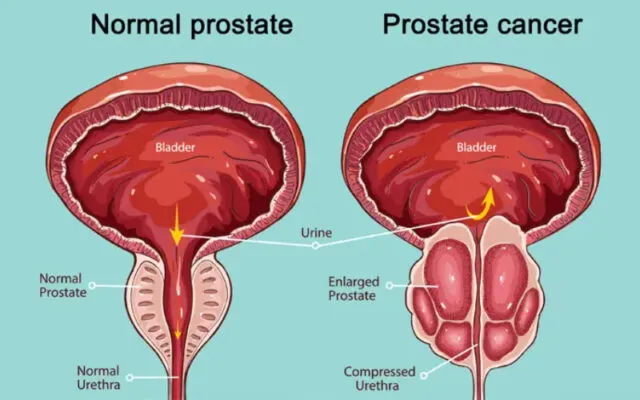

Điều trị u tuyến tiền liệt tại Singapore

Ung thư tuyến tiền liệt là nỗi lo của không ít nam giới, đặc biệt...

U tuyến tiền liệt là gì?

Sức khỏe nam giới, đặc biệt là khi bước vào độ tuổi trung niên, luôn...